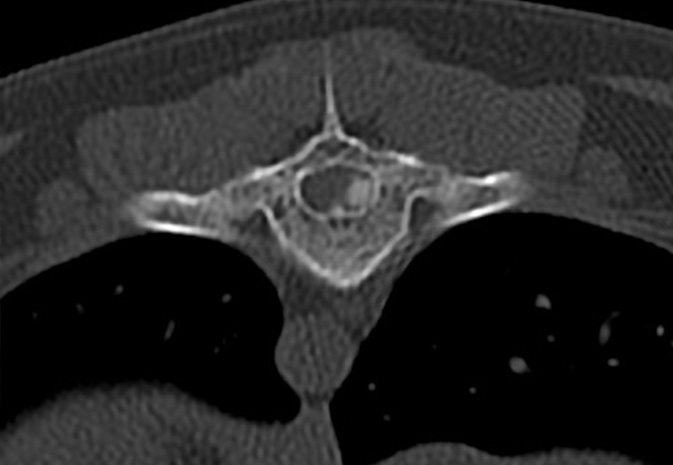

CT Scans